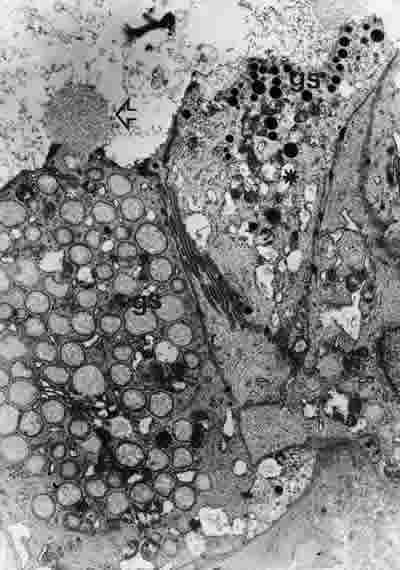

Figura 36

BIOPSIA EN UN PACIENTE CON QCS-GRADO II. LAS CÉLULAS ACINARES (A) TIENEN UN MODERADO NÚMERO DE GRÁNULOS DE SECRECIÓN (gs), QUE EXPULSAN SU CONTENIDO HACIA LA LUZ DEL ACINO (FLECHA ARRIBA). EL NÚMERO DE ORGÁNULOS SUBCELULARES HA DISMINUIDO MODERADAMENTE. MICROSCOPIA ELECTRÓNICA. MAGNIFICACIÓN ORIGINAL X4000.